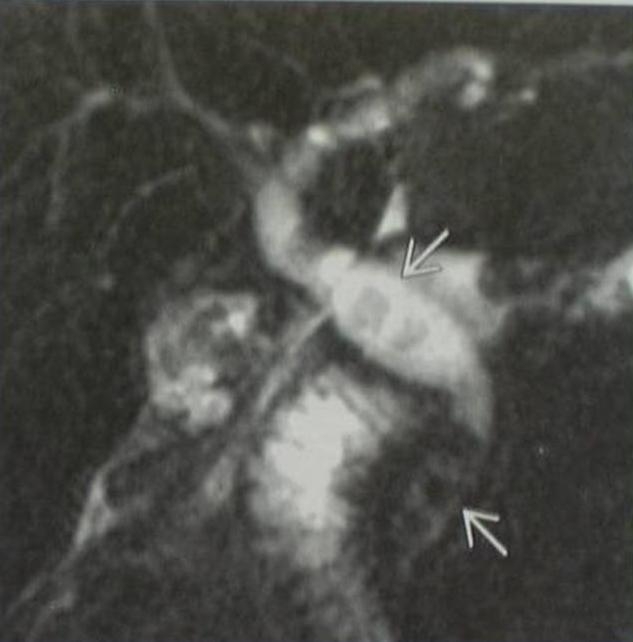

Good news that MR cholangiopancreatography (MRCP – Figure 6) plays an increasingly more important role in the biliary duct imaging since MRCP provides nearly the same image quality as ERCP. In addition, it is extremely important to note that the non-invasive MRCP does not accompany with complications such as pancreatitis or cholangitis which occur in an unneglectible percentage during the ERCP.

Figure 6: MRCP (Magnetic resonance cholangiopancreatography)

MR cholangiopancreatography (MRCP) is only the liquid content of the bile inside the biliary ducts, its imaging is possible because of its no flow. However, the biliary duct is gracile – so in many cases the imaging of the normally dilated biliary ducts is doubtful, but even the slightly dilated intrahepatic (and extrahepatic) biliary ducts and the pancreatic duct(s) can be also exquisitely visualized. The fluid-filled gallbladder is also always visualized. The empty stomach and duodenum is helpful in technical point of view, because the extrapolation of especially the duodenum can be difficult from the imaging of the biliary duct by the rotation of the three-dimensional image. Extent ascites may thwart the examination. Less ascites behaves itself as a "curtain", and you can look behind it only by applying „tricks”. Other fluid-filled cavities do not cause confusion, but the liquor content of the vertebral canal can be deceiving at first glance.

Based on the above mentioned facts, MRCP can be applied in case of biliary duct tumors (malignancy in the liver hilum, Klatskin tumor), intrahepatic or extrahepatic biliary duct strictures or dilatations, investigation of intrahepatic or extrahepatic outflow disorders of unclear origin by other imaging methods, localisation of pancreas head and papilla area processes.

Above all, important to note and apply: MRCP, which is much less threatening to the patient, must be always the first choise before (in most cases pancreatic enzyme failure causing) ERCP (not a foregone intervention)!